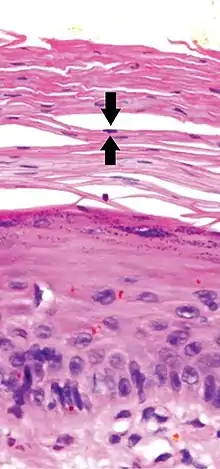

Parakeratosis is a mode of keratinization characterized by the retention of nuclei in the stratum corneum.[1] In mucous membranes, parakeratosis is normal.[2] In the skin, this process leads to the abnormal replacement of annular squames with nucleated cells. Parakeratosis is associated with the thinning or loss of the granular layer and is usually seen in diseases of increased cell turnover, whether inflammatory or neoplastic. Parakeratosis is seen in the plaques of psoriasis and in dandruff.